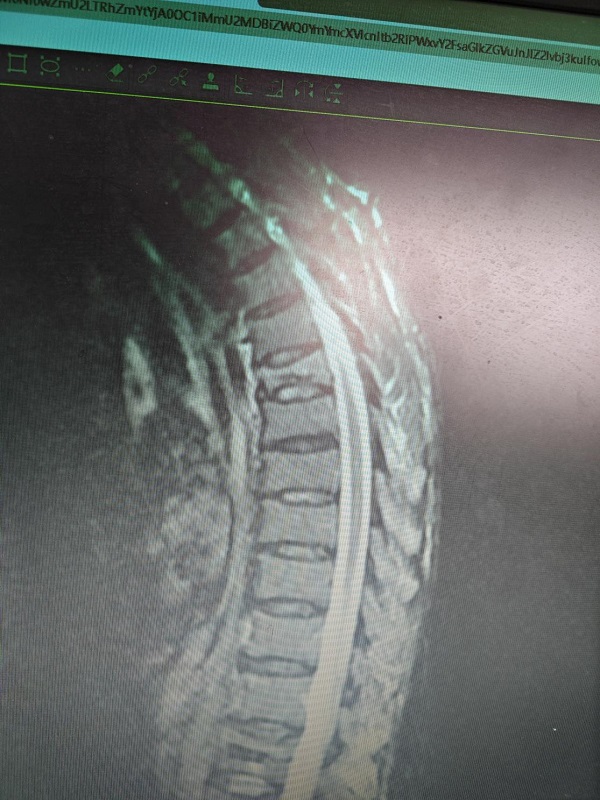

82岁的彭爷爷(化名)是一位地地道道的农民,平日在田土里劳作,生活惬意。然而一次意外跌倒导致他胸6椎体压缩性骨折,剧烈的背部疼痛还有胸部牵涉痛让他非常难受,咳嗽都痛,加上以前有肺心病,这段时间来彭爷爷行走活动差,吃不下饭,连去菜园活动都成了奢望。经检查,彭爷爷被确诊为“胸椎T6节段压缩性骨折”,保守治疗收效甚微,家人慕名来到我院寻求进一步治疗。

我院骨科团队结合彭爷爷的高龄特点和骨质疏松状况及肺心病,支气管扩张等基础疾病,迅速制定了个性化手术方案——椎骨成形术。这种微创技术通过向骨折椎体内精准注入骨水泥,快速稳定椎体、缓解疼痛,具有创伤小、恢复快的特点,尤其适合老年患者。

手术当天,麻醉科团队全程护航,尤其彭爷爷有肺心病,重度支气管扩张,经常气喘、咳嗽,在俯卧位下行高位胸椎手术,既要患者采用先进的局部麻醉联合镇静技术,确保术中患者无痛感,又最大限度减少对心肺功能的影响。在清醒状态下俯卧位轻松配合手术,全程无不适,还与医护人员亲切交谈。仅用30分钟,手术顺利完成。术后X光显示骨水泥填充完美,骨折椎体即刻恢复稳定。

“真神奇!刚做完手术背就不疼了,胸部也不痛了!”术后第二天,彭爷爷已戴护具独立下床行走,笑容满面地竖起大拇指:“现在腰板直了,走路也有劲了,终于能回家抱孙子了!”出院前复查显示,彭爷爷的胸椎高度完全恢复,疼痛缓解明显,生活质量显著提升。